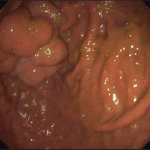

Endoscopic Duodenal Mucosal Resurfacing